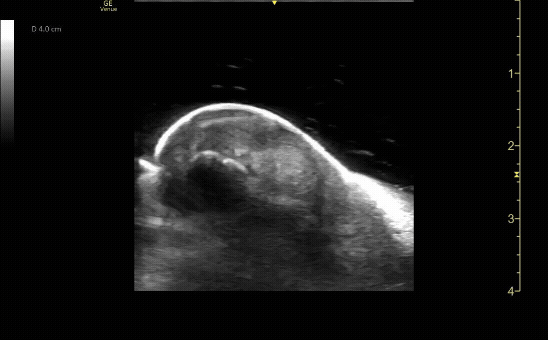

Sagittal view of achilles tendon rupture.